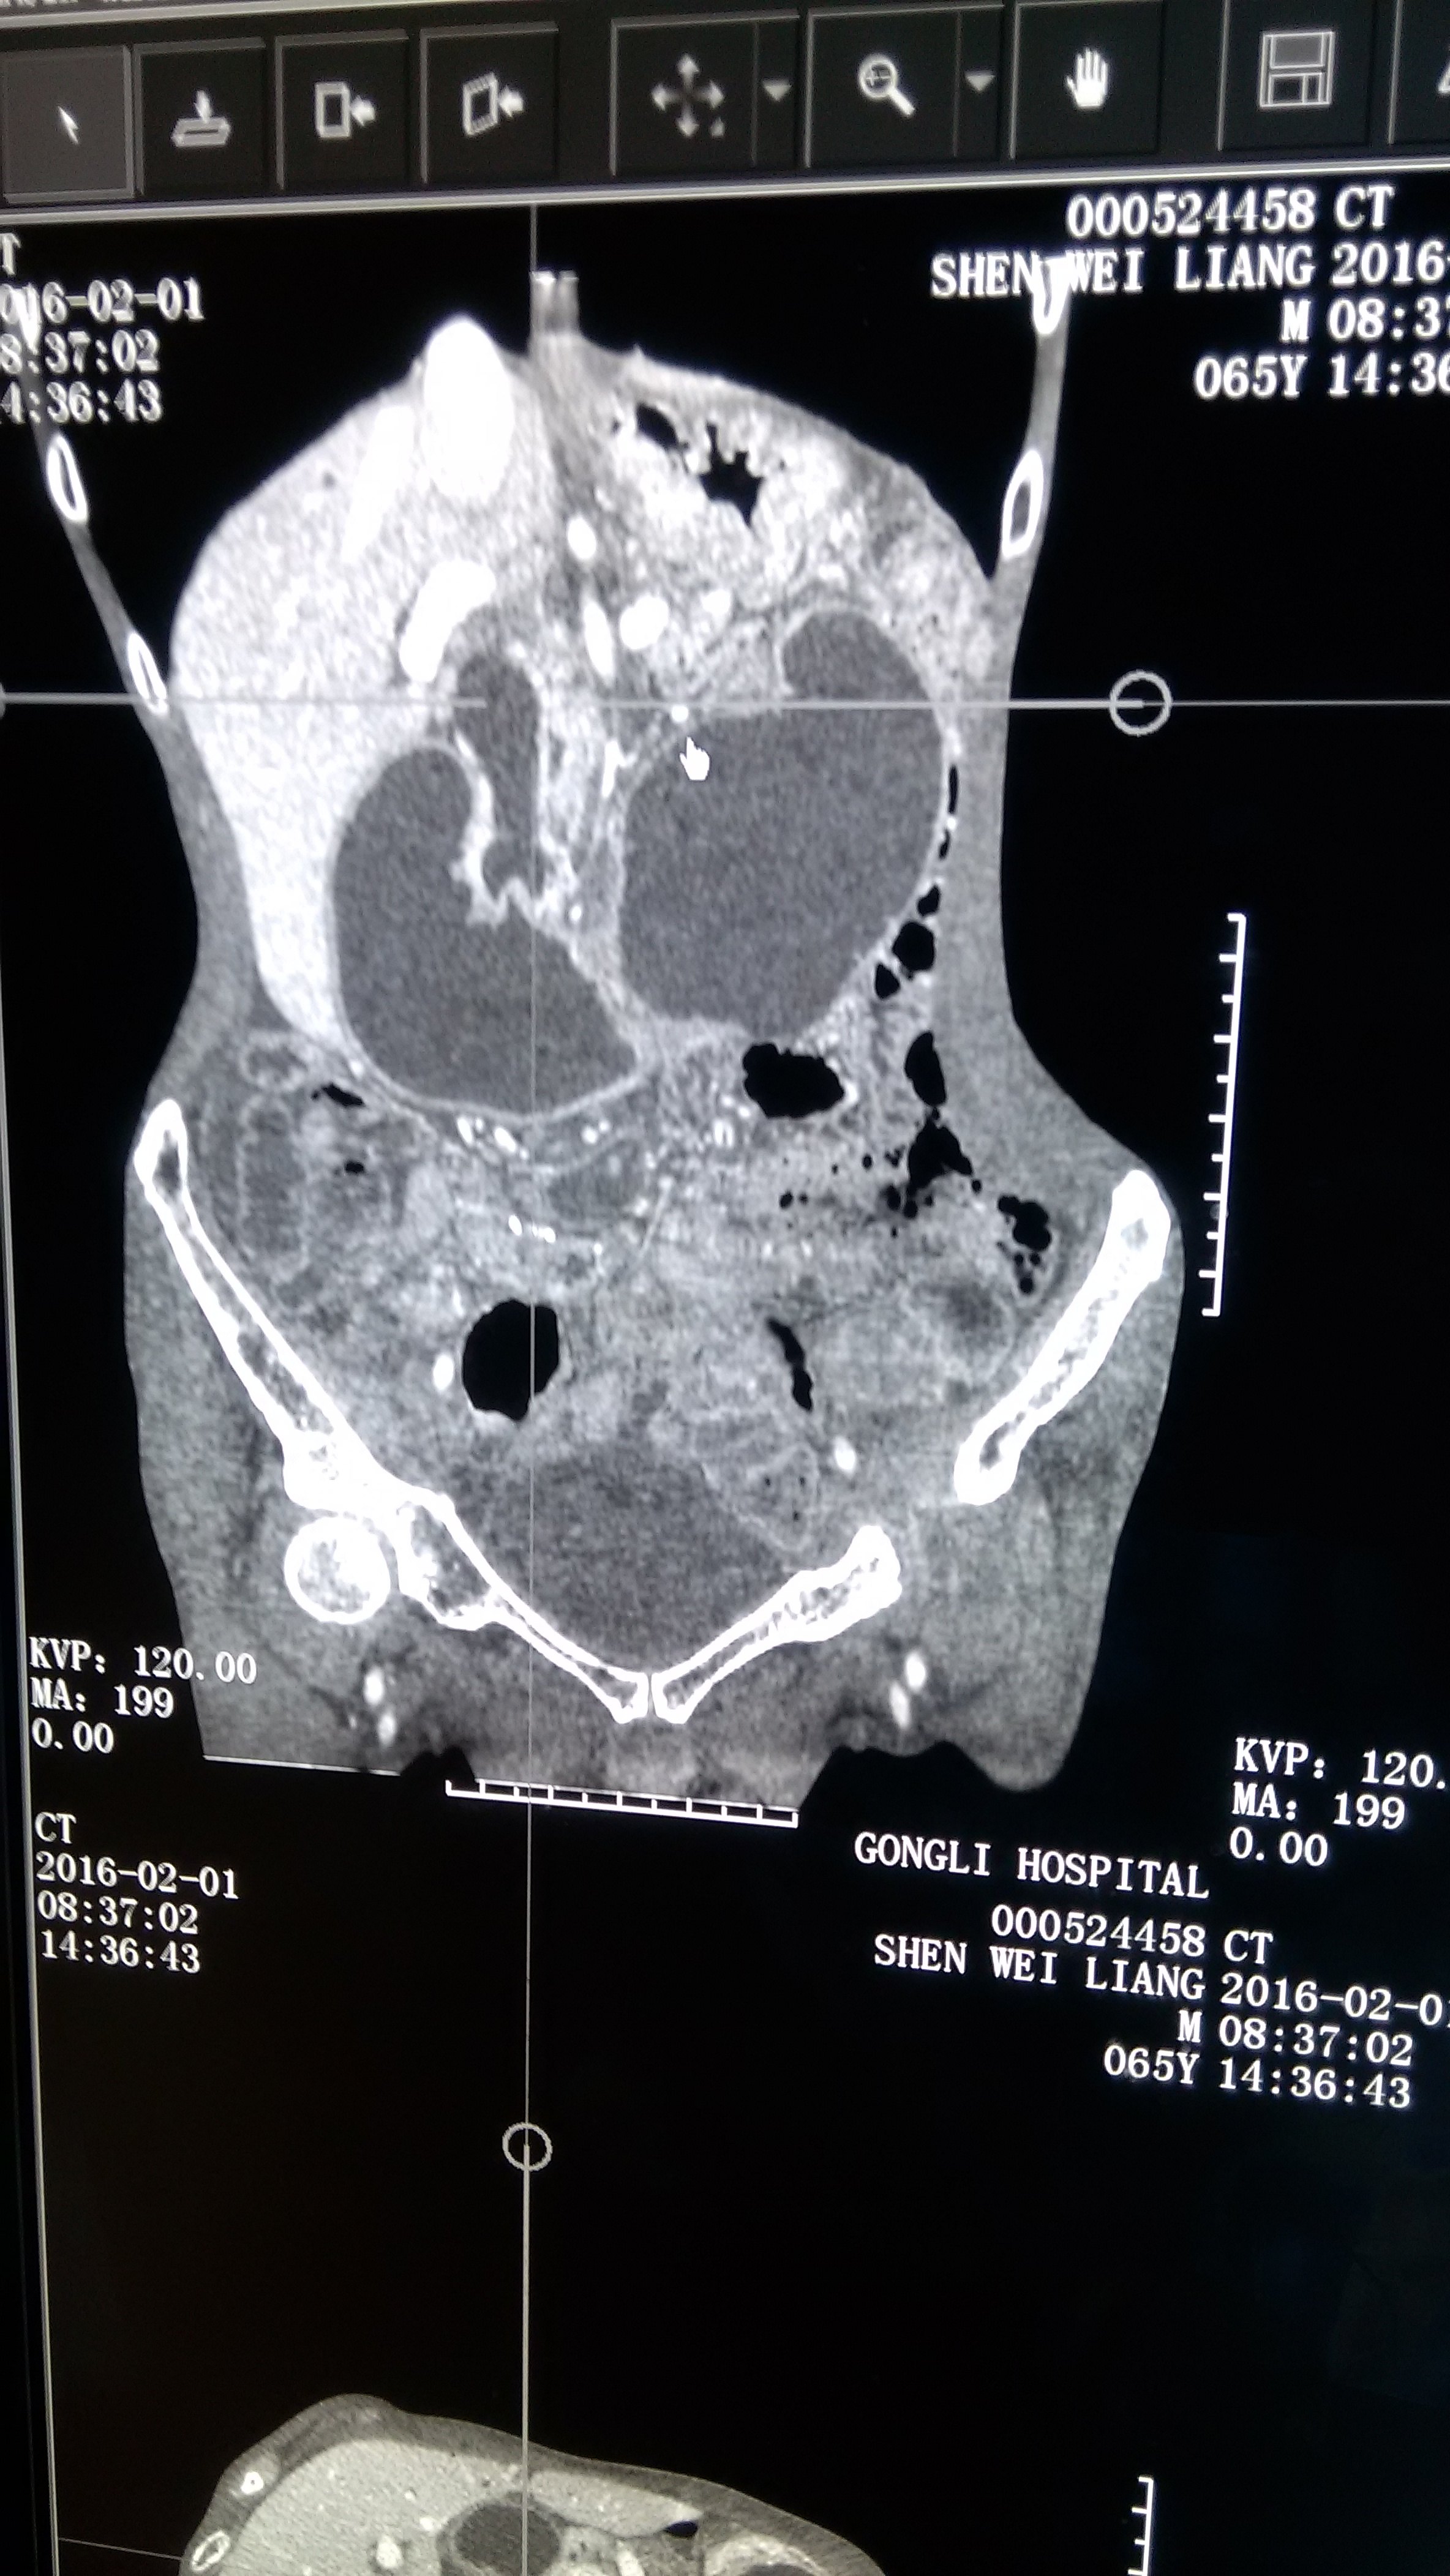

胆肠吻合输入袢结石并输入袢肠梗阻,胆管炎